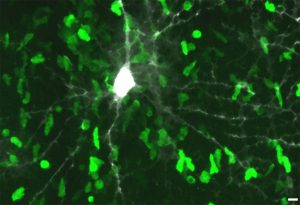

Mehr erfahren zu: "Erstmals früher Schritt der zellulären Störung bei Alzheimer erkannt" Erstmals früher Schritt der zellulären Störung bei Alzheimer erkannt Überaktive Nervenzellen in bestimmten Hirnbereichen gelten als eine frühe Erscheinung bei Alzheimer. Erstmals gelang es einem Team der Technischen Universität München (TUM), die Gründe und Mechanismen dieses anfänglichen und damit […]